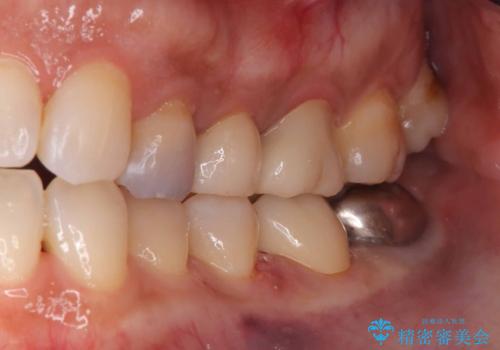

1歯はオールセラミッククラウンもう1歯はセラミックインレーで治療を行いました。

- 税込209,000円(オールセラミッククラウン121,000円+仮歯11,000円+セラミックインレー77,000円)費用は治療当時の料金となります

当院ではセラッミクインレーをつける時は必ずラバーダムを使用して付けます。

唾液と湿気はセラミックインレーの接着を阻害するのでラバーダムを使用しそれを防ぎます。